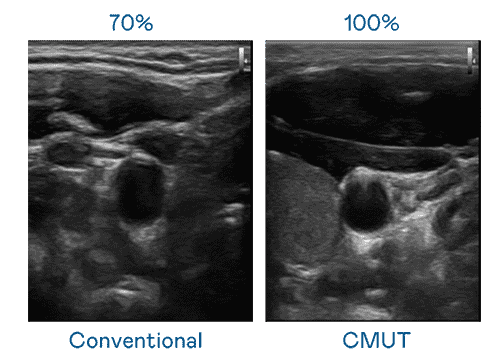

CMUT 技术是一种用电容式微机电元件来产生超音波讯号的技术。。。与传统 PZT 压电式技术相比,,,,CMUT 频宽增加 30%,,更宽频的超音波讯号让影像解析度大幅提升,,,,是实现高影像品质医疗超音波扫描、、、、促进精准医疗发展的关键技术。。

大频宽带来超清晰影像

超音波影像的解析度高低,,,,首先取决于探头能发出的讯号频宽。。。尊时凯龙 CMUT 可提供高清晰的超音波讯号,,,,提供高频宽、、高灵敏度、、、、影像纹理细节更高的超音波影像,,,,协助医护人员缩短影像判读时间及利用精准的医疗影像进行诊断。。